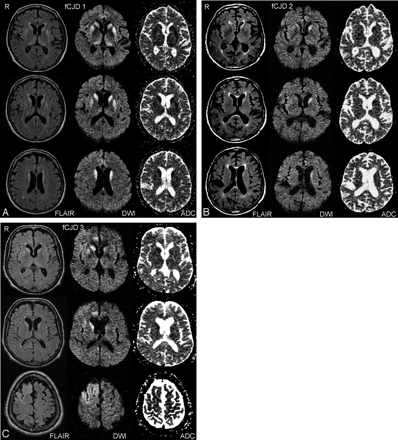

Representative imaging findings on FLAIR, DWI, and ADC sequences in 3 different subjects with familial CJD. In A (fCJD 1), signal intensity abnormality involves the caudate nucleus, putamen, and thalamus, bilaterally. B (fCJD 2) demonstrates abnormal signal intensity primarily in the left caudate nucleus. In C (fCJD 3), there is involvement of both caudate nuclei, right greater than left, right cingulate gyrus, and right frontal lobe.

The contingency analysis demonstrated that MR imaging is sensitive to fCJD caused by the E200K mutation (on-line Table). Twenty of the 61 brain regions demonstrated significant differences between CJD subjects and controls in one of these regions on at least one of the imagining sequences. These regions included the frontal lobe gray matter, frontal lobe white matter, parietal lobe gray matter, occipital lobe gray matter, occipital lobe white matter, cingulate gyrus gray matter, hippocampus, insula, caudate nucleus, putamen, globus pallidus, and thalamus (Fig 1). The brain regions involved in the highest percentage of fCJD cases in any single sequence were as follows: the caudate nuclei with FLAIR (12 subjects, 80%), the caudate nuclei with DWI (11 subjects, 73%), the putamen with DWI (10 subjects, 67%), the putamen with FLAIR (9 subjects, 60%), the thalamus with DWI (6 subjects, 40%), and the cingulate gyrus with DWI (6 subjects, 40%). Imaging findings in cortical gray matter were best detected with DWI and were seen in the frontal gray matter (4 subjects, 27%) and the occipital gray matter (3 subjects, 20%). There were no signal intensity abnormalities in the cerebellum that differentiated fCJD patients and control subjects. fCJD subjects had some degree of atrophy, though cortical and ventricular volumes were not quantified in this study. Two of 15 fCJD patients did not demonstrate signal intensity abnormalities on MR imaging in this blind analysis (except mild atrophy) and were considered to be false-negative by MR criteria (Fig 2, see Discussion). In 2 control subjects, the signal intensity changes seen in the caudate, putamen, and thalamus were focal areas of hyperintensity most consistent with small-vessel ischemic disease and lacunar infarcts.